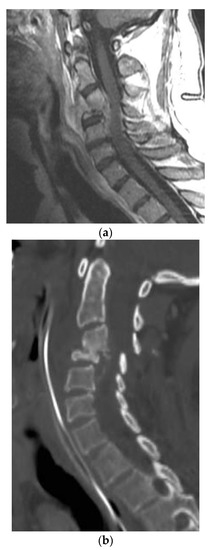

A 28-year-old man presented with a one-month history of lower back pain, worsening shortness of breath, and intermittent fevers over a period of the month. He was initially treated with azithromycin at an outside facility, which failed to resolve his symptoms. The back pain was progressively severe and radiated to both lower extremities, limiting his ambulation. He had no history of sick contacts, travel, or history of exposure to tuberculosis patients. Initial treatment included empiric antibiotics and screening tests for HIV, tuberculosis with PCR, legionella, and a endemic mycosis serology panel that included histoplasmosis, blastomycosis, and coccidioidomycosis. A CT scan of the chest revealed lucencies throughout mid-thoracic spine with adjacent prominence of paraspinal soft tissues suggestive of osteomyelitis and discitis. MRI of the T spine revealed abnormal marrow enhancement seen with varying degrees of paraspinal soft tissue enhancement, the most significant being at T6 where diffuse marrow enhancement and vertebral height loss was seen (Figure 1a,b). A biopsy of the lesion confirmed the coccidioidomycosis (Figure 1c). He was initiated on antifungal therapy—voriconazole and amphotericin B—followed by surgical debridement and stabilization.

Figure 1. (a) Axial T1-weighted magnetic resonance (MR) images with contrast showing extensive vertebral body and soft tissue enhancement with compression of the spinal canal at T6. (b) Sagittal T1-weighted MR Images with contrast showing extensive enhancement throughout the vertebral bodies and soft tissue but most significantly at T6–7. (c) Hematoxylin and eosin (H&E) staining of the thoracic bone specimen showing acute osteomyelitis with abundant coccidioides organisms. Multinucleated giant cells with engulfed coccidioides spherules is a characteristic finding. Abundant acute inflammatory changes was noted in the marrow cavity.